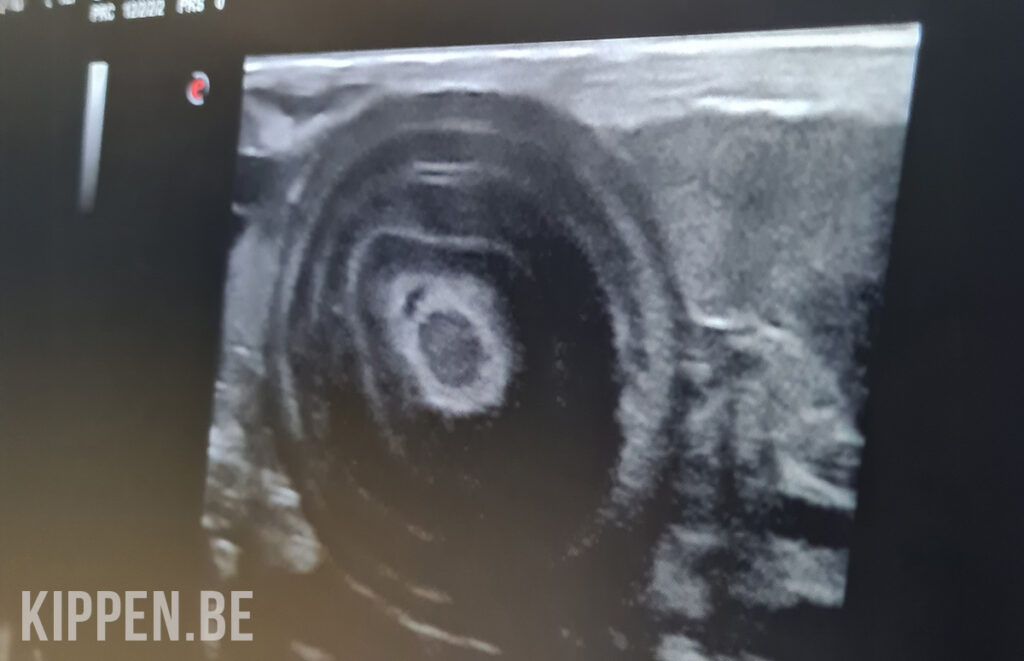

Je kan ook een echografie aanvragen bij je dierenarts. De onsteking is dan duidelijk te zien in de eileider van de kip: